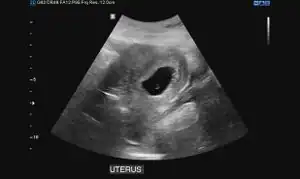

Obstetric ultrasonography may also be used to detect and diagnose pregnancy. It is very common to have a positive at home urine pregnancy test before an ultrasound. Both abdominal and vaginal ultrasound may be used, but vaginal ultrasound allows for earlier visualization of the pregnancy. With obstetric ultrasonography the gestational sac (intrauterine fluid collection) can be visualized at 4.5 to 5 weeks gestation, the yolk sac at 5 to 6 weeks gestation, and fetal pole at 5.5 to 6 weeks gestation. Ultrasound is used to diagnose multiple gestation.[3][19]

Ultrasound: early pregnancy -

Ultrasound: failed early pregnancy

Ultrasound is also a common tool for determining viability and location of a pregnancy. Serial ultrasound may be used to identify non-viable pregnancies, as pregnancies that do not grow in size or develop expected structural findings on repeated ultrasounds over a 1-2 week interval may be identified as abnormal.[34] Occasionally, a single ultrasound may be used to identify a pregnancy as non-viable; for example, an embryo that is greater than a certain size but that lacks a visible heart beat may be confidently determined to be not viable without the need for follow up ultrasound for confirmation.[34]